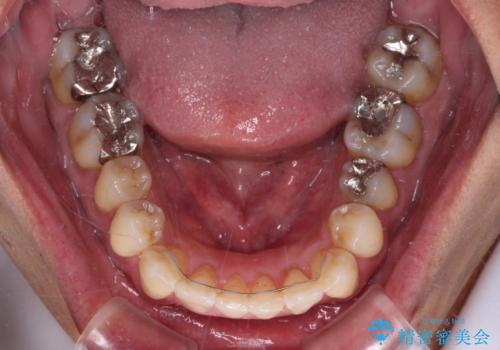

- 前歯のデコボコを気にして来院された患者様です。

下顎前歯のデコボコが特に強く、治療を早く終えることを考えるとワイヤー装置がお勧めですが、ワイヤー装置の異物感は避けたいのでインビザラインを希望されていました。

下顎にワイヤー装置を装着し、暫くしたところでやはりインビザラインにて矯正治療をしたいとのことで、インビザラインに切り替えました。

短い期間でしたがワイヤー装置を使用したことでデコボコが解消されたため、インビザラインの比較的短い期間で矯正治療を行うことができました。